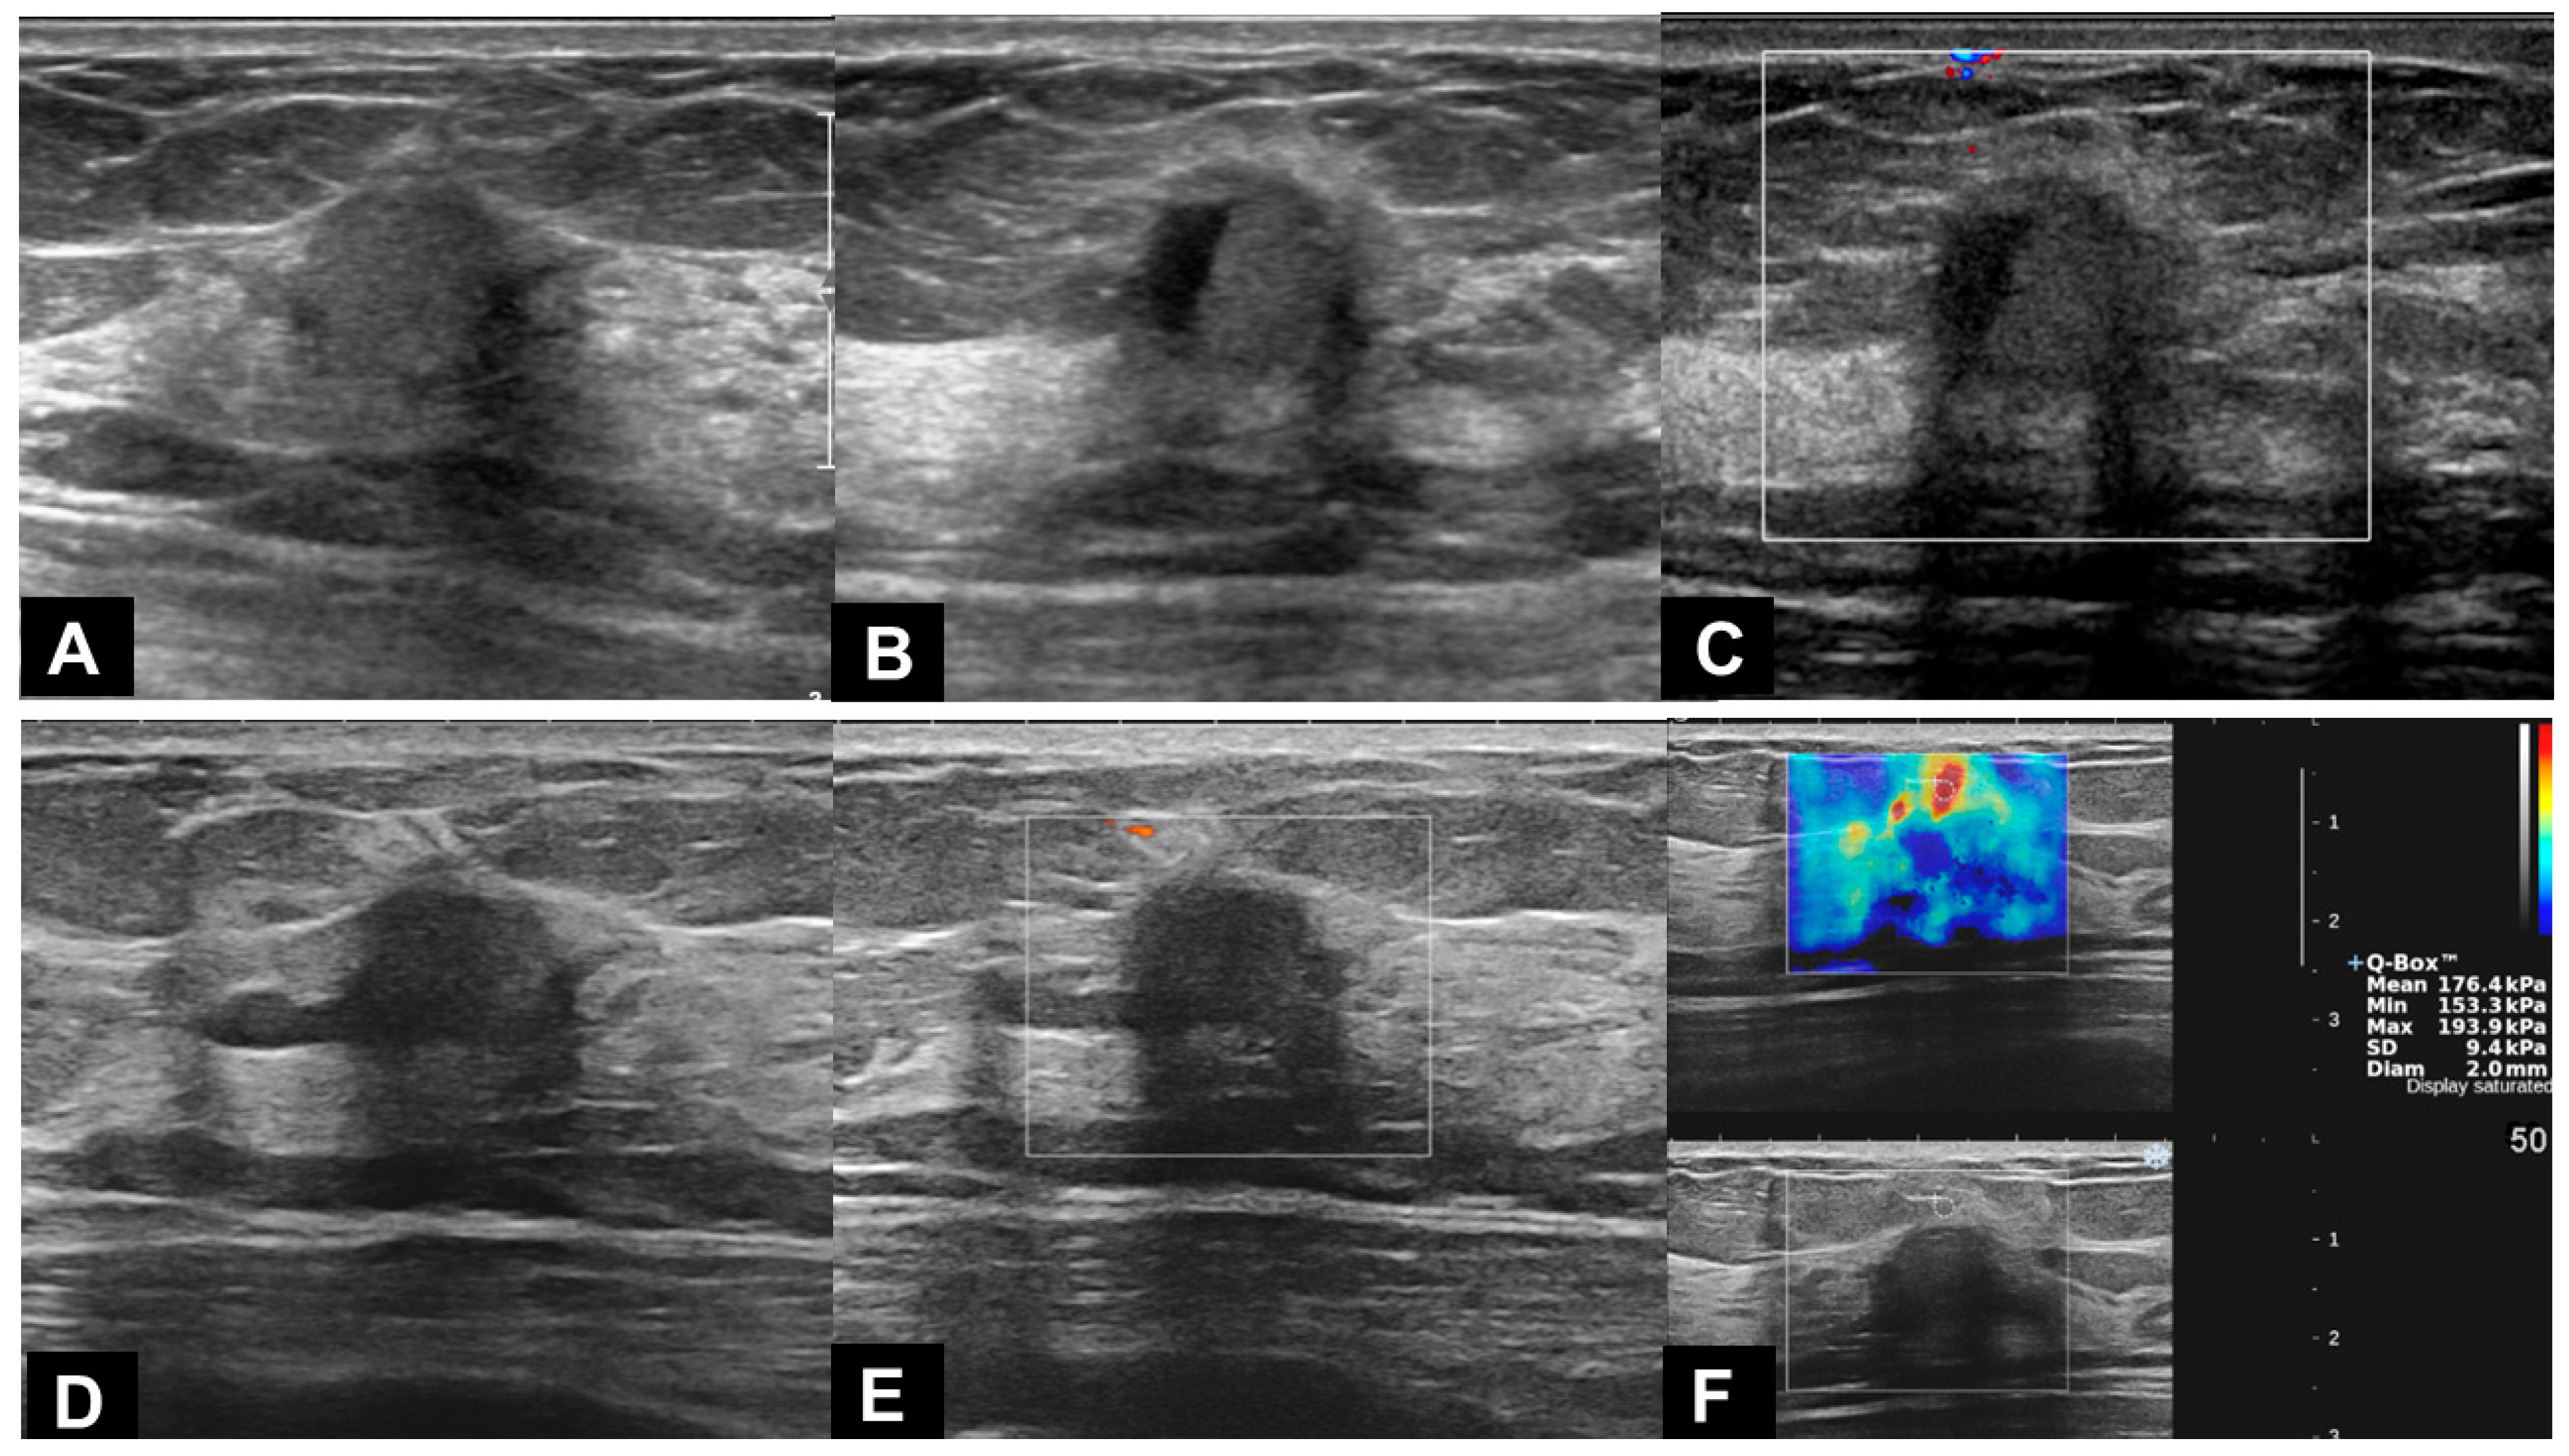

| Mass | 18/18 (100.0%) |

| Non-mass lesion | 0/18 (0.0%) |

| Size (cm, median) | 0.8 (0.6, 1.1) |

| Shape | |

| Round or oval | 9/18 (50.0%) |

| Tubular | 1/18 (5.6%) |

| Irregular | 8/18 (44.4%) |

| Margin | |

| Circumscribed | 8/18 (44.4%) |

| Not circumscribed | 10/18 (55.6%) |

| Echogenicity | |

| Hypoechoic | 3/18 (16.7%) |

| Isoechoic | 8/18 (44.4%) |

| Hyperechoic | 7/18 (38.9%) |

| Echogenic halo | 5/18 (27.8%) |

| Taller-than-wide | 11/18 (61.1%) |

| Posterior acoustic shadowing | 3/18 (16.7%) |

| Hypervascularity | 4/18 (22.2%) |

| Location | |

| Skin~subcutaneous layer | 3/17 (17.6%) |

| Subcutaneous layer | 2/17 (11.8%) |

| Subcutaneous layer~breast parenchyma | 9/17 (52.9%) |

| Breast parenchyma | 3/17 (17.6%) |

| BI-RADS category | |

| 3 | 7/18 (38.9%) |

| 4A | 9/18 (50.0%) |

| 4B | 1/18 (5.6%) |

| 4C | 1/18 (5.6%) |

| Decrease in size | 9/12 (75.0%) |

| No change | 3/12 (25.0%) |

| Increase in size | 0/12 (0.0%) |